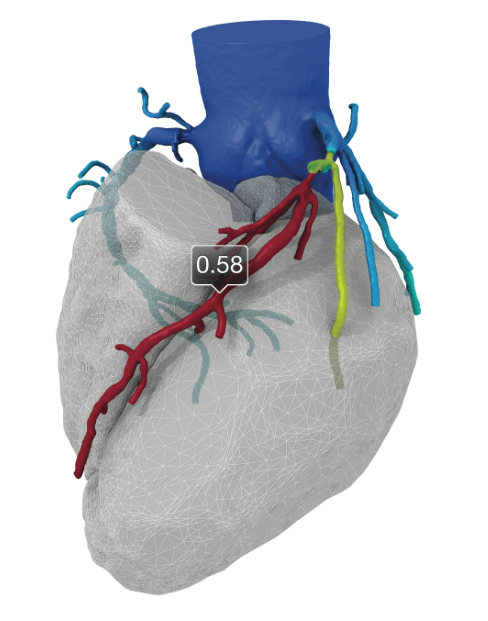

The technology, developed by HeartFlow, Inc. is the first and only noninvasive diagnostic test specifically designed to provide cardiologists with both anatomic and functional information regarding the extent and significance of coronary artery blockages. It takes coronary CTA scans and combines them with proprietary computer algorithms based on computational fluid dynamics to create a color-coded, 3-D model of the patient's three major coronary arteries, showing both derived FFR information and anatomy. FFR-CT is calculated as a distal-to-proximal pressure ratio, just as it is derived from invasive measurements in the catheterization lab.

The level of detail in this noninvasive test allows the team to determine which patients truly require a catheterization or revascularization, allowing for more efficient use of resources and a better experience for patients.

"The beauty of it is that there's no special scanner or special protocol," says Hiram Bezerra, MD, PhD, Director of the Cardiovascular Imaging Core Laboratory of UH Harrington Heart & Vascular Institute at UH Cleveland Medical Center. "It's based on a standard CTA that you do every day. By combining the CTA with a physiological assessment, unnecessary catheterizations based previously on false-positive stress tests can be avoided."

"In the new value-based healthcare environment, FFR-CT offers significant advantages over our current screening tests," adds Sri Krishna Madan Mohan, MD, Chief Quality Officer with UH Harrington Heart & Vascular Institute. "We not only reduce the number of tests, radiation exposure and total costs, but we improve patient outcomes by revascularizing patients with functionally important coronary artery disease."